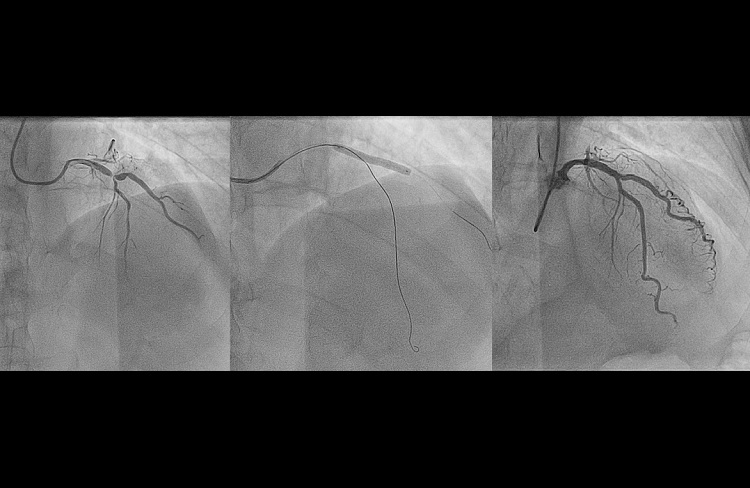

- diagnostyka inwazyjna choroby wieńcowej oraz ostrych zespołów wieńcowych (koronarografia);

- zabiegi przezskórnej angioplastyki wieńcowej (PTCA) w świeżym zawale serca oraz stabilnej chorobie wieńcowej;

- zabiegi rotablacji wieńcowej w uwapnionych blaszkach miażdżycowych;

- diagnostykę zmian granicznych stwierdzonych w trakcie koronarografii (zwężenia 40-70%), przy pomocy oceny czynnościowej zwężeń (FFR) oraz oceny morfologicznej (ultrasonografii wewnątrzwieńcowej -IVUS);

- zarówno zabiegi diagnostyczne, jaki i terapeutyczne wykonywane są w większości z dostępu od tętnicy promieniowej, rzadziej od tętnicy ramiennej i w niewielkim odsetku od pachwiny (tętnicy udowej, < 3%).

Pracownia wykonuje szeroką gamę zabiegów diagnostycznych i leczniczych w obrębie łożyska płucnego, krążenia wieńcowego oraz wad strukturalnych serca. W pracowni wykonywane są zabiegi zarówno w trybie ostrodyżurowym (w ramach 24 godzinnego ostrego dyżuru hemodynamicznego) oraz kompleksowe zabiegi w trybie planowym. Specjalizujemy się w nowoczesnych dostępach naczyniowych u chorych poddawanych koronarografii (dystalny dostęp od tętnicy promieniowej oraz łokciowej) co skutkuje znikomą liczbą powikłań oraz krótkim pobytem w oddziale szpitalnym. U pacjentów z silnie uwapnionymi zwężeniami w tętnicach wieńcowych, u których klasyczna przezskórna angioplastyka jest nieskuteczna wykonujemy z powodzeniem rotablację (zabieg wykonywany z zastosowaniem wysokoobrotowego wiertła diamentowego modyfikującego blaszkę miażdżycową, rocznie > 25 zabiegów co plasuje nasz ośrodek w gronie liderów tej metody w Polsce- system Rotablator – Rotational Angioplasty System, Boston Scientific). Dzięki współpracy z Kliniką Medycyny Transplantacyjnej, Nefrologii i Chorób Wewnętrznych skutecznie i bezpiecznie leczymy inwazyjnie chorych z zaawansowanymi postaciami niewydolności nerek.